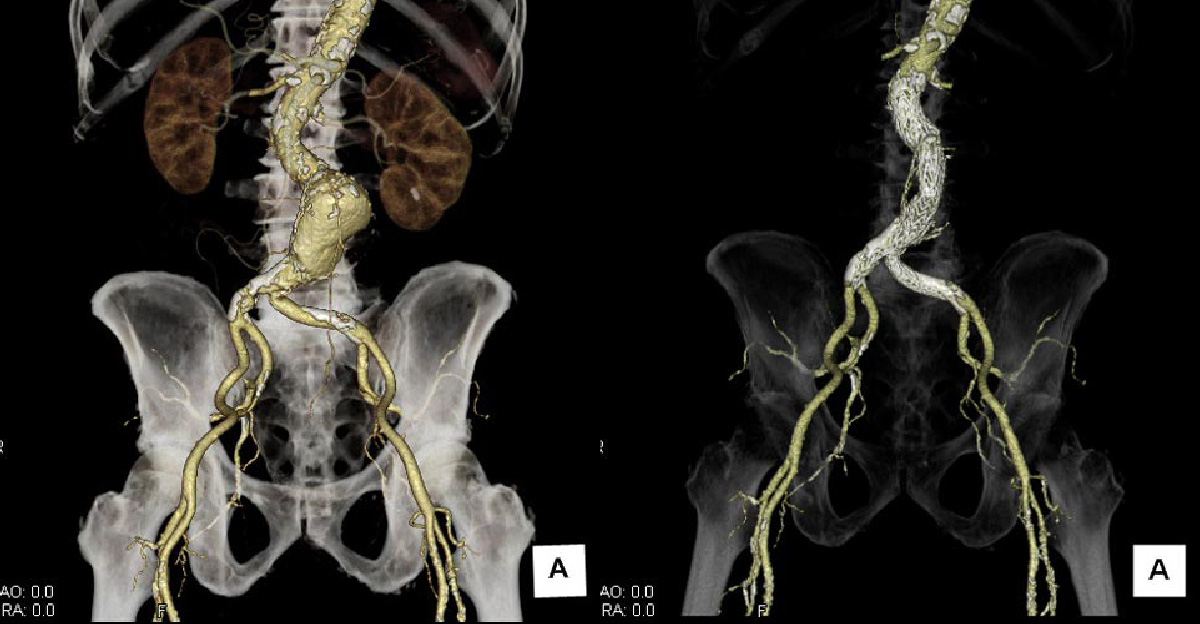

大動脈瘤

破裂すれば即死することもあり、リスクとなる高血圧、高脂血症、喫煙者、高血圧、高脂血症、糖尿病の患者さんは発症に注意が必要です。

腎動脈遠位に発症した、最大短径50mm以上に増大した腹部大動脈瘤。

左:術前 右:ステントグラフト留置術後